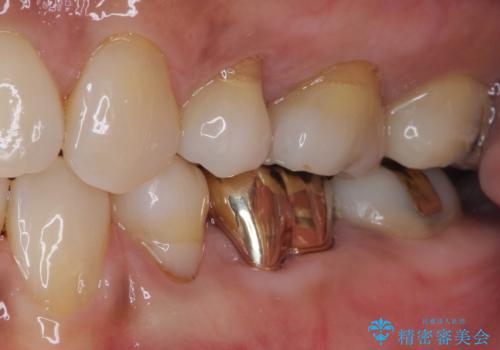

ゴールドは「白い歯」ではありませんが、銀歯の金属色とは異なり、非常にきれいな色合いが特徴です。

もちろん、適合が極めて良いという圧倒的メリットもゴールドクラウンやゴールドインレーの特徴です。